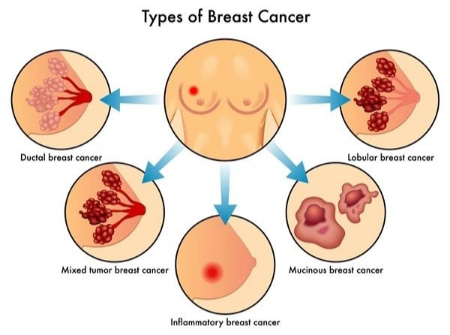

سرطان سینه نوعی سرطان است که از بافت سینه شروع می شود. علائم رایج سرطان سینه عبارتند از:

سرطان سینه اغلب باعث تغییرات پوستی در سینه ها می شود. علائم احتمالی پوستی سرطان سینه عبارتند از:

سرطان التهابی سینه: نوعی نادر و تهاجمی

سرطان التهابی سینه نوعی سرطان است که تنها حدود 1 تا 5 درصد از کل موارد سرطان سینه را تشکیل می دهد. این نوع سرطان، شکل نادری از کارسینوم مجرای مهاجم است و نسبت به انواع دیگر سرطان سینه تهاجمیتر رفتار میکند. سرطان التهابی سینه به دلیل مسدود شدن عروق لنفاوی توسط سلولهای سرطانی و ایجاد التهاب، باعث ایجاد تغییراتی در پوست سینه میشود.

علائم سرطان التهابی سینه عبارتند از: